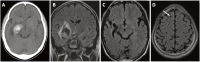

Results: Secondary brain tumors occurred in 21% of cases: 10% were cavernomas, 6% were meningiomas, 3% were skull osteomas, and 1% were anaplastic astrocytoma. The cumulative proportion of developing secondary brain tumor was 6% at 10 years and 20% at 20 years, while the cumulative proportion for developing cavernomas and meningiomas was 16% and 7% at 20 years, respectively.

Conclusion: Our study shows that patients who received cranial irradiation were at risk of secondary brain tumors such as cavernomas and meningiomas. Thus, a meticulous follow-up of cancer survivors with history of cranial irradiation by an annual MRI scan is justifiable. This will help clinicians to detect secondary brain tumors early and make its management much easier.